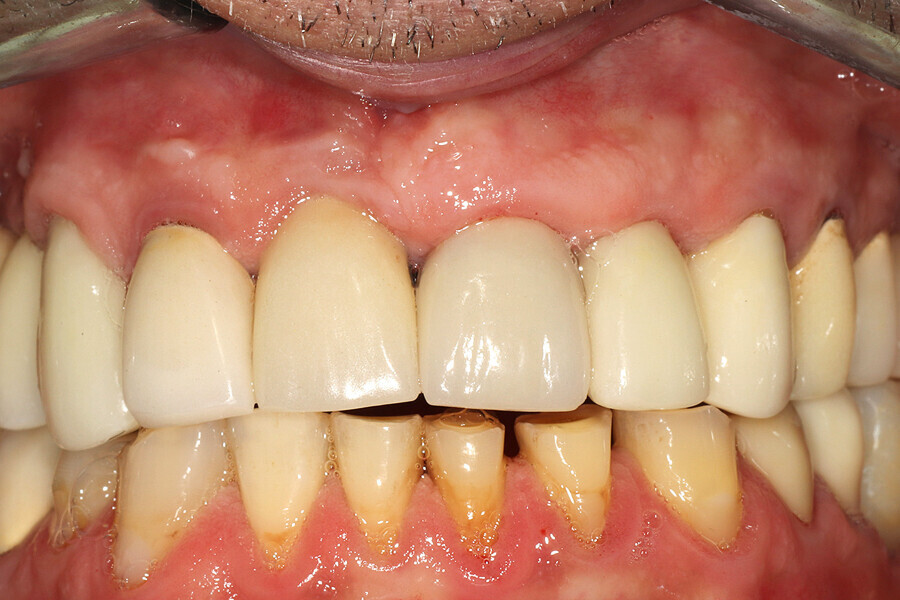

Fig. 29: The definitive restoration exhibited excellent retention of the soft-tissue profile.

Fig. 30a: The occlusal view revealed the volume maintained with

the soft-tissue cervical contours (a), and the lateral retracted view revealed an excellent soft-tissue emergence profile (b).